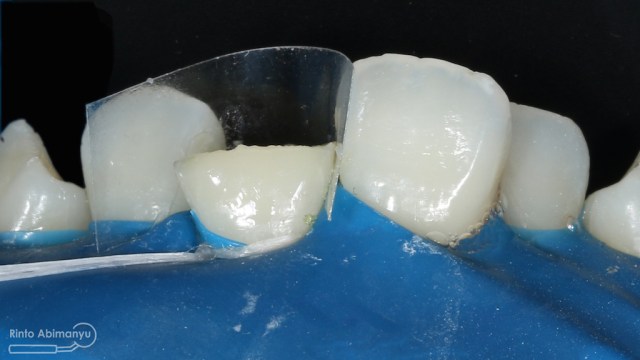

Untuk kunjungan pertama ini saya rencanakan melakukan perawatan saluran akar langsung pada dua gigi central… Saya pasang rubber dam untuk mengisolasi daerah kerja

Gigi 11 21 setelah dipasang rubber dam

Akses kamar pulpa dilakukan pada kedua gigi, dan penjajakan saluran menggunakan K-file nomer 10.. Kemudian pengukuran panjang kerja menggunakan apex locator Root ZX mini (Morita).. Preparasi saluran akar pada gigi insisiv tidak memerlukan waktu lama karena saluran akarnya yang sudah lebar, sehingga waktu yang terpakai lebih banyak untuk aktivasi irigasi, pada kasus ini saya menggunakan larutan irigasi NaOCl 5,25% dan diaktivasi menggunakan alat sonik waterpik dengan tip endoactivator….

Kondisi gigi setelah selesai cleaning and shaping